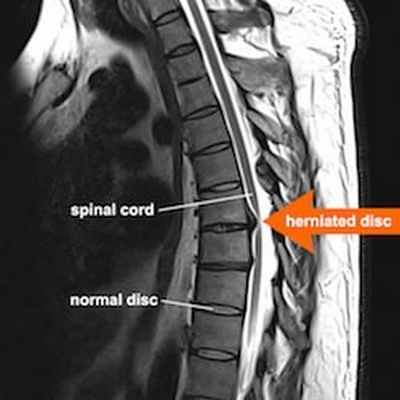

Одной из самых частых находок на МРТ позвоночника является межпозвоночная грыжа, которая чаще всего располагается в шейном или пояснично-крестцовом отделах и реже в грудном. Она может проявляться клинически болью на том или ином участке спины, а может проходить бессимптомно. Боль в спине служит одним из самых частых поводов обращения к неврологу, при этом данный симптом присущ многим дегенеративным заболеваниям позвоночника от спондилеза до обычного мышечного спазма или дефанса. Поэтому так часто по результатам первичного неврологического осмотра врач назначает для дифференциальной диагностики проведение МРТ позвоночника. Метод магнитно-резонансной томографии является высокоинформативным в исследовании позвоночных структур . Его достоинствами являются неинвазивность, безвредность для пациента, высокая разрешающая способность, возможность получения послойных изображений в различных проекциях. Данные томографии позволяют охарактеризовать особенности структуры тел позвонков и межпозвоночных дисков, дают возможность выявить наличие и определить величину протрузий и грыж межпозвоночных дисков, обнаружить элементы компрессии структур позвоночного канала, определить состояние связочного аппарата, выявить наличие реактивного асептического воспаления (в случае грыжевых выпячиваний, сопровождающихся выраженными компрессионными эффектами).

Грыжа межпозвоночных дисков - это локализованное смещение тканей диска за пределы нормальных границ дискового пространства. Любое выпячивание межпозвонкового диска в просвет канала обычно атрибутируется как грыжа. В медицинских центрах неврологи и рентгенологи в своем заключении грыжи подразделяют по виду выпячивания на основании типа смещения тканей диска. Грыжа диска может принимать формы «протрузии» или «экструзии».

Протрузия диска – это межпозвоночная грыжа диска (грыжевое выпячивание/смещение тканей диска), в которой самое большое расстояние в любой плоскости между краями смещенного за пределы дискового пространства материала диска меньше, чем расстояние между краями основания смещенной ткани в той же самой плоскости (у основания всегда больше, чем в конечной его части).

Признаки грыжи- экструзии на МРТ

Экструзия диска – это грыжа, при которой по крайней мере в одной плоскости любое расстояние между краями материала диска, находящегося вне дискового пространства, является большим, чем расстояние между краями основания в той же самой плоскости.

При подозрении на грыжу МРТ покажет очень точно:

- морфологию грыжи (протрузия, экструзия и т.д.);

- локализацию выпячивания в позвонке;

- непрерывность, объем (размер) и протяженность межпозвоночной грыжи;

- взаимосвязь с комплексом задней продольной связки;

- структуру грыжи (сигнальные характеристики).

Также томография позвоночника показывает наличие или отсутствие компрессионного воздействия на невральные структуры (спинномозговой корешок), дуральный мешок, его содержимое и хорошо визуализирует просвет позвоночного канала, перифокальные изменения на уровне дегенеративно измененного межпозвоночного диска.